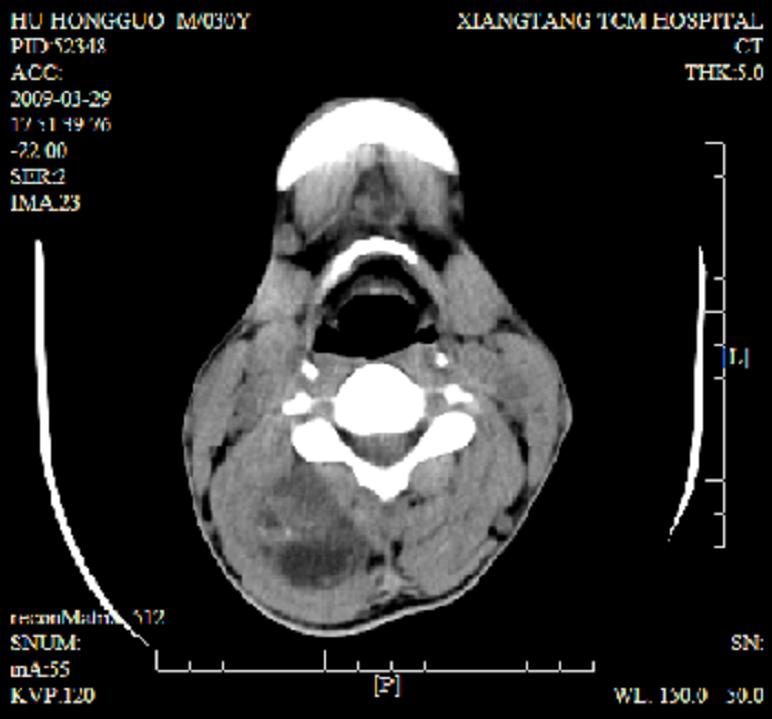

标题: CT19102:颈部肿块

男30y发现肿块3年

多处囊实性肿块,形态欠规则有一定形态,内见点状钙化,以囊变为主,增强后轻度强化,首先考虑神经源性肿瘤如鞘瘤,不除外脉管源性肿瘤如淋巴管瘤(见缝钻及囊性区域太多,如果合并感染完全可以这个影像表现),和海绵状血管瘤,但是血管瘤不太支持因为强化特征和病灶形态不典型.

右侧椎前间隙后部肌间、皮下囊性为主病变,可见分隔和点状钙化,分隔和壁呈轻度环形强化,大部分无强化。形态不规则,有钻缝特点。考虑1 淋巴管瘤合并感染2 血管平滑肌脂肪瘤3 表皮样囊肿4 不除外海绵状血管瘤。